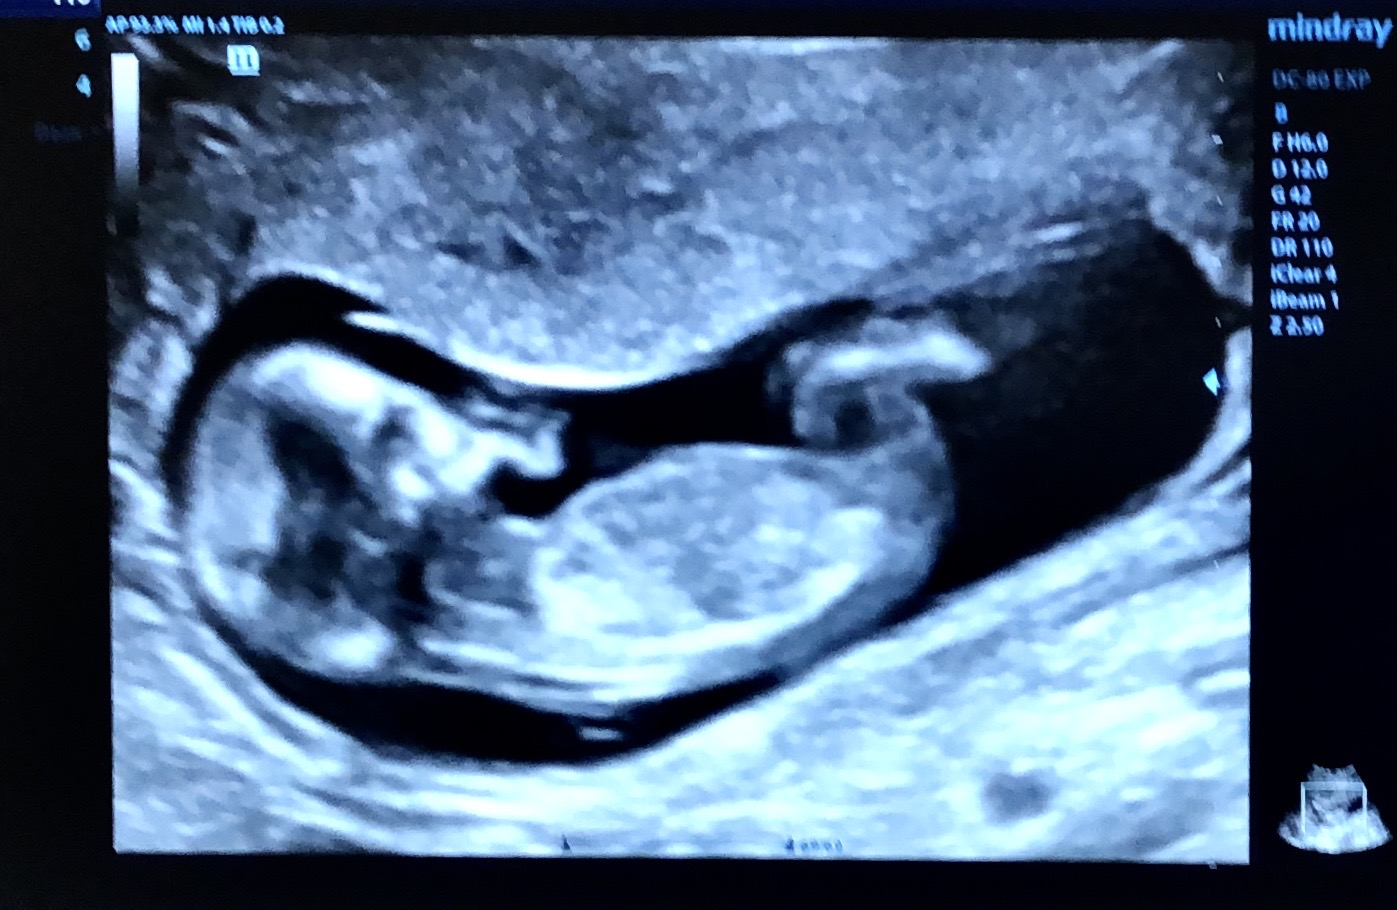

Скрининг прошел успешно🌸🥳

Так прям ногу на ногу сложил 😅

Тут на фото нет полового бугорка, поэтому не сказать.

Ишь какой/ая деловой/ая - сидит нога на ногу😁!! Ничего не рассмотреть

Ножками закрыл бугорок.

Бугорка не видно😊

Не понятно ещё.

Девочка возможно, серцебиение мальчика за 160 обычно, но может и ошибаюсь 🫶